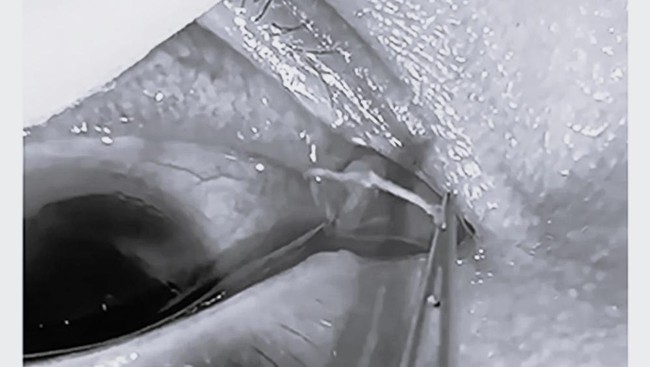

Saat dokter menggunakan alat retraktor kelopak mata, mereka menemukan empat cacing putih kecil merayap di area tersebut. Pasien diberikan anestesi topikal untuk menghilangkan rasa sakit sebelum cacing diangkat menggunakan forsep.

Cacing yang diambil lalu dikirim ke laboratorium untuk dianalisis secara mikroskopis dan genetik. Hasil pemeriksaan menunjukkan itu adalah Thelazia callipaeda, atau cacing mata oriental, penyebab infeksi parasit yang dikenal sebagai thelaziasis.

Setelah memastikan tidak ada cacing tersisa, dokter membilas mata pasien dengan larutan khusus dan memberikan salep antibiotik untuk mencegah infeksi lanjutan.